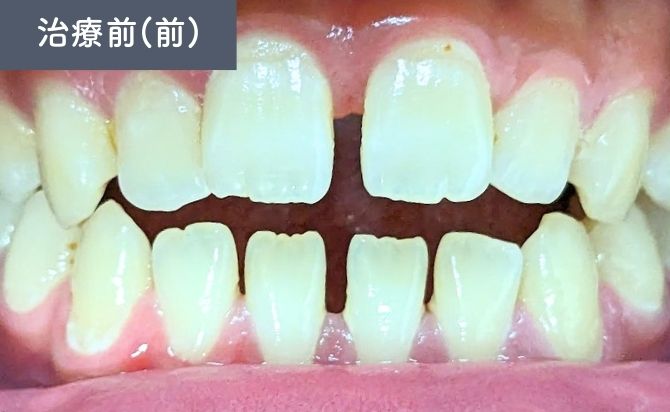

診察では、上顎左右1番間の歯間空隙(すきっ歯)が認められ、審美面での改善希望が強い症例でした。また、前歯部では上下の噛み合わせが接触しない開咬(オープンバイト)の状態が確認されました。

上下前歯には軽度の前突傾向があり、歯列弓の乱れによって歯間空隙と噛み合わせの不安定さが生じている状態でした。

歯並びの変化(正面)